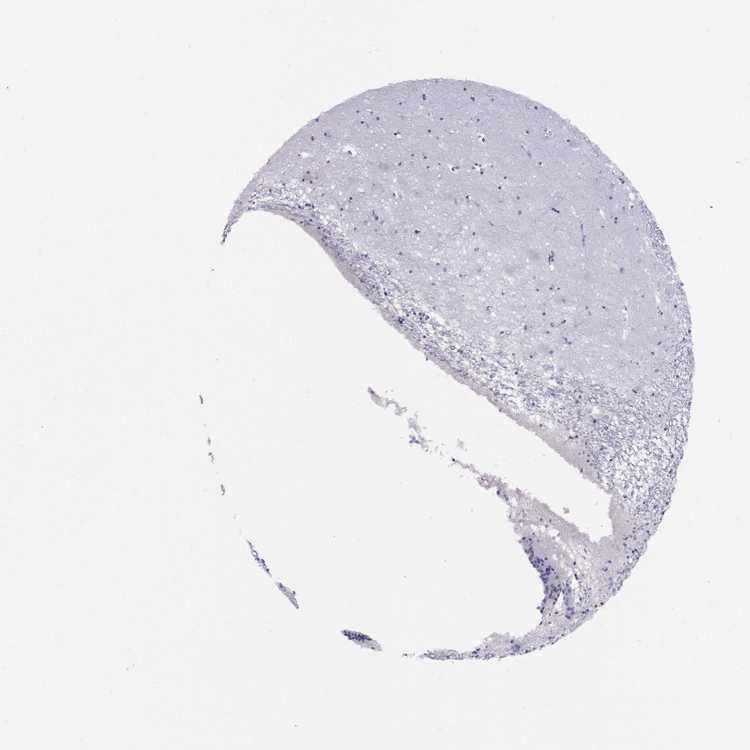

CAUDATE - Antibody stainingi

Antibody staining in the annotated cell types in the current human tissue is reported as not detected, low, medium, or high, based on conventional immunohistochemistry profiling in selected tissues. This score is based on the combination of the staining intensity and fraction of stained cells.

Each image is clickable and will lead to virtual microscopy that enables deeper exploration of all samples and also displays staining intensity scores, fraction scores and subcellular localization as well as patient and tissue information for each sample.

Antibody HPA035881

Glial cells Not detected

Neuronal cells Low